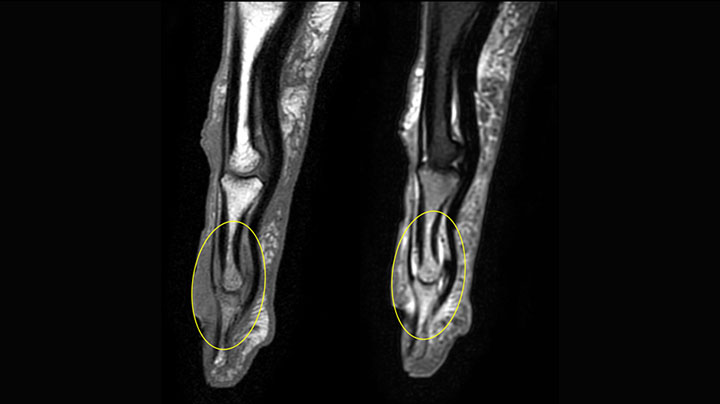

The Prodiva shoulder coil is very flexible and has large coverage, which makes good positioning easier, and that contributes to the superb image quality and high SNR that we get in our shoulder exams.

Scan time 2:55 min, FOV 160 mm, acq voxels 0.55 x 0.83 x 3.0 mm.

Scan time 4:19 min, FOV 160 mm, acq voxels 0.55 x 0.80 x 3.0 mm.

Scan time 2:50 min, FOV 160 mm, acq voxels 0.70 x 0.99 x 3.0 mm.